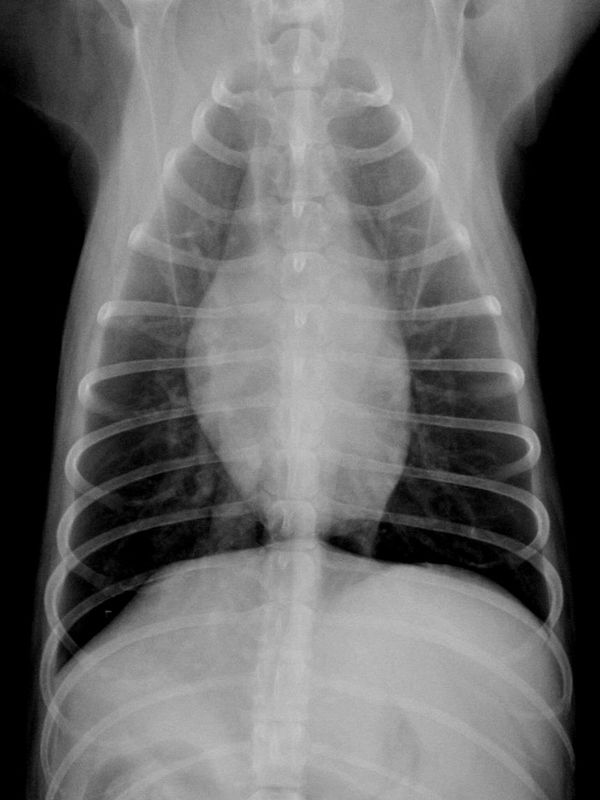

2/15/18犬の心臓肥大の症状とは? 原因と治療法、余命、食事の知識 心臓病 犬の病気 心臓病 犬の心臓病で心臓肥大というのはよくある病気です。 心臓肥大というのは心臓が通常の状態よりも大きくなっていることです。 症状が進行している状態では余命が数ヶ月という場合もありますので、早めに治療することが必要です。 心臓が肥大することでどのような. 以下のような検査を行い、心臓の状態を調べていきます。 聴診:心臓音(雑音の程度)、呼吸音を調べます。 レントゲン検査:心臓の肥大の程度や血管に異常がないかなどを調べます。 心電図検査:電気的流れから波形の異常や不整脈などを調べます。. この病気は進行するとX線検査や心臓エコー検査で心臓の拡大が認められます。 今回はX線検査での心臓の拡大の評価方法の1つである「VHS」についてご説明致します。 VHS(Vertebral Heart Size):胸骨心臓サイズ VHS とは胸部 X 線検査で心臓の拡大の程度を簡単に評価する方法です。 まず、心臓の長軸(赤線: L )を測定し、第 4 胸椎から椎骨何個分に相当するか.

5/31/17レントゲン 心臓の形や肥大していないかなどをみます。 超音波 心臓の血液の流れ、壁の厚さなどの状態をみます。 血液検査 心不全によって起こる肝臓や腎臓の機能の低下や、多血症になっていないかを調べる。 血圧測定 血圧の変化をみる。. 7/13/18胸のレントゲン写真で心臓の大きさを測ってみよう! 18年7月13日 admin 放射線科 最近、死亡原因としてテレビなどでよく耳にする 「心不全」 という言葉がありますが、病名だと思っている方が多いのではないでしょうか? 実は、 「心不全」 という言葉は病気の名前ではなく、心臓のポンプ機能が低下し身体のあらゆるところへと影響が及んだ状態を言います. 犬の心臓病で一番多い病気は僧帽弁閉鎖不全症です。 そして、この地域で特に多く見かけるのはフィラリア症です。 僧帽弁閉鎖不全症は防ぐことができませんが、フィラリアは予防することができます。 猫で多い心臓の病気は心筋症です。 また、猫でもフィラリアにかかると言われています。 これらの病気の診断には、レントゲン、心電図、血液検査、心エコー.

5/27/18犬のレントゲン撮影にかかる平均的な費用 犬のレントゲン撮影検査の1回の平均費用は、小型~中型犬で5,000~10,000円、大型~超大型犬で8,000~15,000円となります。 ただし、犬のレントゲン検査を緊急時に夜間救急病院や救急病院にて受ける場合、検査や処置の他に、夜間料金(8,000円~)、緊急対応料金(5,000円~)などの費用が別途かかります。 また緊急時には. 心疾患 動物たちの長寿化に伴い、心疾患の動物たちが増えてきています。 一言で“心疾患”と表現しても、その病態は様々です。 それぞれの心臓に合わせた治療法を実施する必要があります。 心臓の評価は、レントゲン検査、超音波検査、全身状態 (心拍数・呼吸状態・脱水・体重の増減)、血液検査、心電図検査などで行います。. レントゲン検査 左心肥大 心臓エコー検査 右側からの傍胸骨短軸・大動脈レベルにて肺動脈内にモザイクを認める 全収縮期性のプローブに向かう乱流 診断 pda(動脈管開存症) 治療 動脈管結紮術をお.